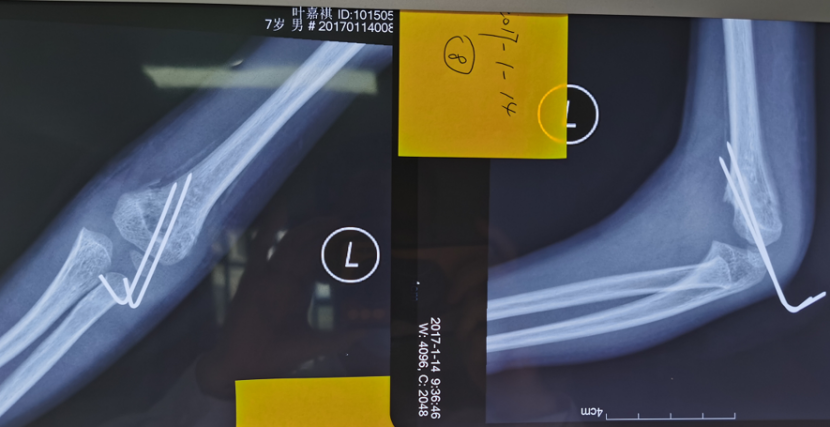

手术后X线片

该例患者虽行手术治疗,但从术后X线片上分析其骨折端旋转畸形矫正不充分,残余肱骨远端的内旋畸形,所以术后逐渐发生肘内翻畸形。针对该患者我们实施了手术矫形治疗。